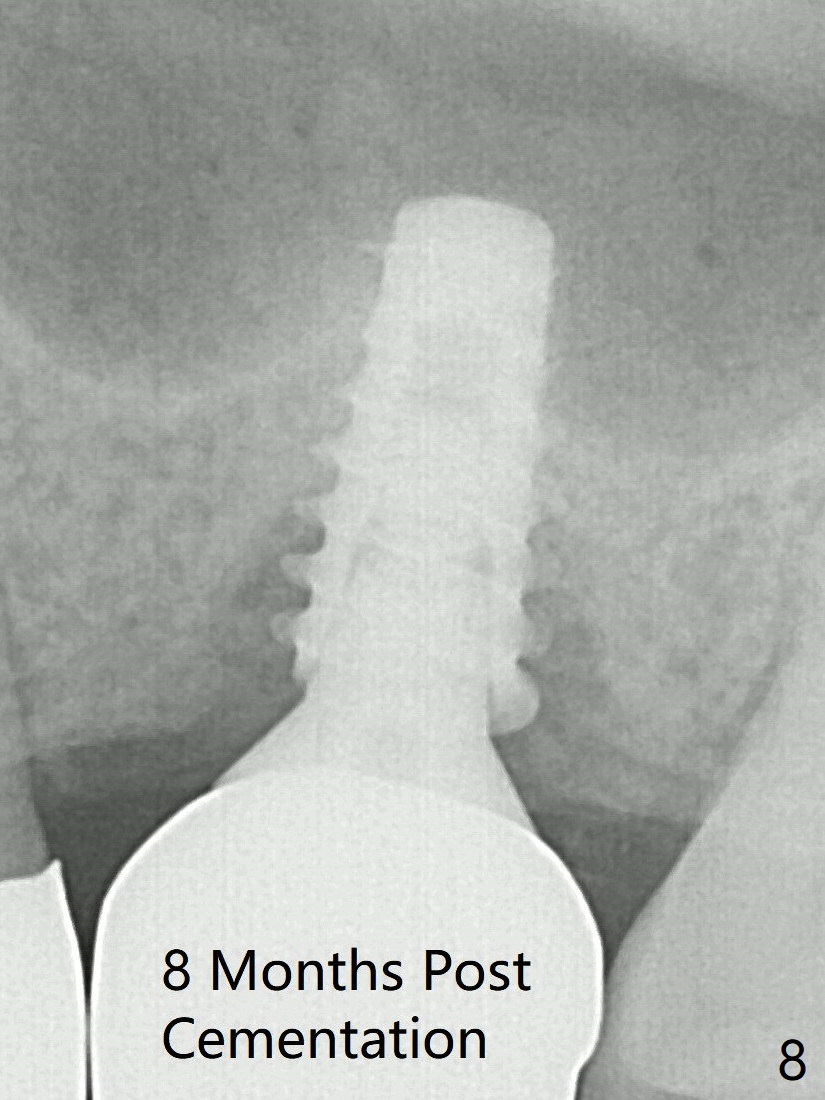

After insertion of a 4.5x11 mm dummy implant at 9 mm (35 Ncm; for further bone expansion), one piece of PRF plug and 1 piece of PRF membrane are pushed into the osteotomy, followed by allograft mixed with autogenous bone for sinus lift (*) and placement of a 5x9 mm implant (Fig.3,4 with insertion torque >50 Ncm). The implant appears to have been placed too deep. In fact a BW shows otherwise. There is mild bone resorption at the crest 11 months postop (Fig.7 *). Although the sinus lift with bone graft becomes less distinct, there is more implant/bone contact mesial (arrow). The bone resorption seems to be worse 8 months post cementation (Fig.8,9); in fact the abutment screw is loose. The gingiva is healthy.